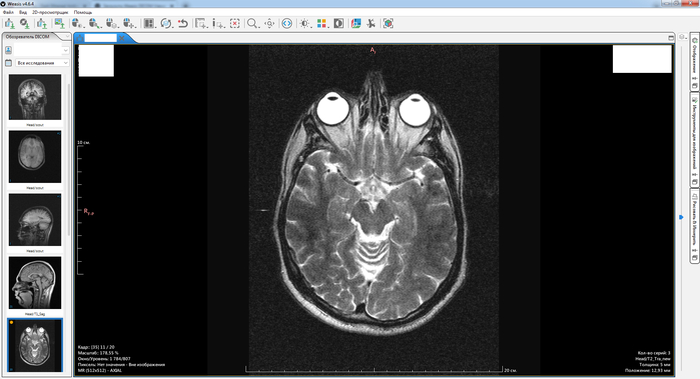

Собственно вопрос, к тем кто разбирается, действительно ли на данных снимках нет грыжи?

Снимки (с экрана) ниже. Откликнувшихся заранее благодарю.